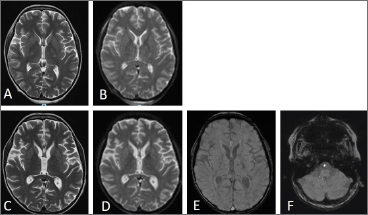

An 18-years-old non-ambulant male on daily steroids treatment since the age of four, with a history of delayed puberty, severe osteoporosis, and vertebral deformities. Following a car rear-end collision with no apparent injuries, the patient developed an acute anxious state accompanied by vertigo, vomiting and tachycardia, which rapidly progressed to cardiopulmonary shock and coma. He was initially admitted to a local Emergency Department (ED), where a femoral fracture was not suspected. Brain CT imaging was unremarkable, chest CT revealed bilateral cotton-like opacities, predominantly in the posterior-inferior regions, accompanied by interstitial congestion (Fig. 1-A). The patient was urgently transferred to our hospital in critical condition with respiratory and hemodynamic instability, requiring orotracheal intubation and ICU admission for advanced support due to acute left ventricular dysfunction. Although the rapid progression to multiorgan failure raised suspicion of acute myocarditis, cardiac MRI did not confirm this diagnosis. Given the patient’s history of a car accident, a lower limb X-ray was performed due to suspicion of fat embolism syndrome (FES), which confirmed the presence of a distal suprametaphyseal fracture of the right femur. The clinical suspicion was further supported by additional clinical and laboratory findings, including thrombocytopenia and anemia, which required red blood cell and plasma transfusions. Retinal hemorrhages were also noted, along with the gradual appearance of bilateral thalamocapsular lesions (Fig. 2). During a prolonged ICU stay, the patient was gradually weaned from mechanical ventilation. Neurological status progressively improved, ultimately resulting in full recovery of both motor and cognitive functions.

Figure 2. Brain MRI of Patient #1. (A, B) MRI 9 days after trauma: bilateral T2 iperintense lesions located in the bilateral thalamo-capsular nucleus (A); areas of diffusion restriction in left thalamo-capsular nucleus (B), compatible with fat embolism. (C,D,E) MRI one month after the traumatic injury: reduction of previously evident T2 bilateral nucleo-thalamo-capsular signal alterations (C) and absence of restriction of diffusivity (D); multiple punctate hypointensities in magnetic susceptibility images (SWI) with diffuse subcortical and deep bihemispheric localization, bilateral thalamocapsular nucleus, and in the subtentorial area, suggestive of fat embolism (E,F).